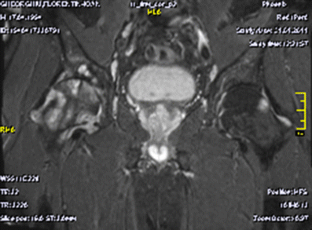

Pigmented villonodular synovitis (PVNS) is a rare, benign proliferative disease of the synovial tissue that affects a single joint or a tendon sheath. Data from the literature present only a few cases of multifocal PVNS. This paper presents multifocal PVNS in the adult. This disease can affect bilateral shoulders, hips and knees. The diagnosis may be delayed by the slow evolution of the disease (up to ten years); some patients may be seen with late-stage degenerative joints, serious complications, painful and functionally uncompensated, with significant locomotion deficit. PVNS requires a radical treatment with prosthetic arthroplasty associated with synovectomy. Complex imaging (X-Rays, magnetic resonance imaging (MRI), ultrasound) and macroscopic appearance of the lesions during surgery confirms the clinical diagnosis of multifocal PVNS with secondary bone lesions. Histology marks the final diagnosis of multifocal PVNS. The postoperative results are good, with recovery in functional parameters of the joints with endoprosthesis.